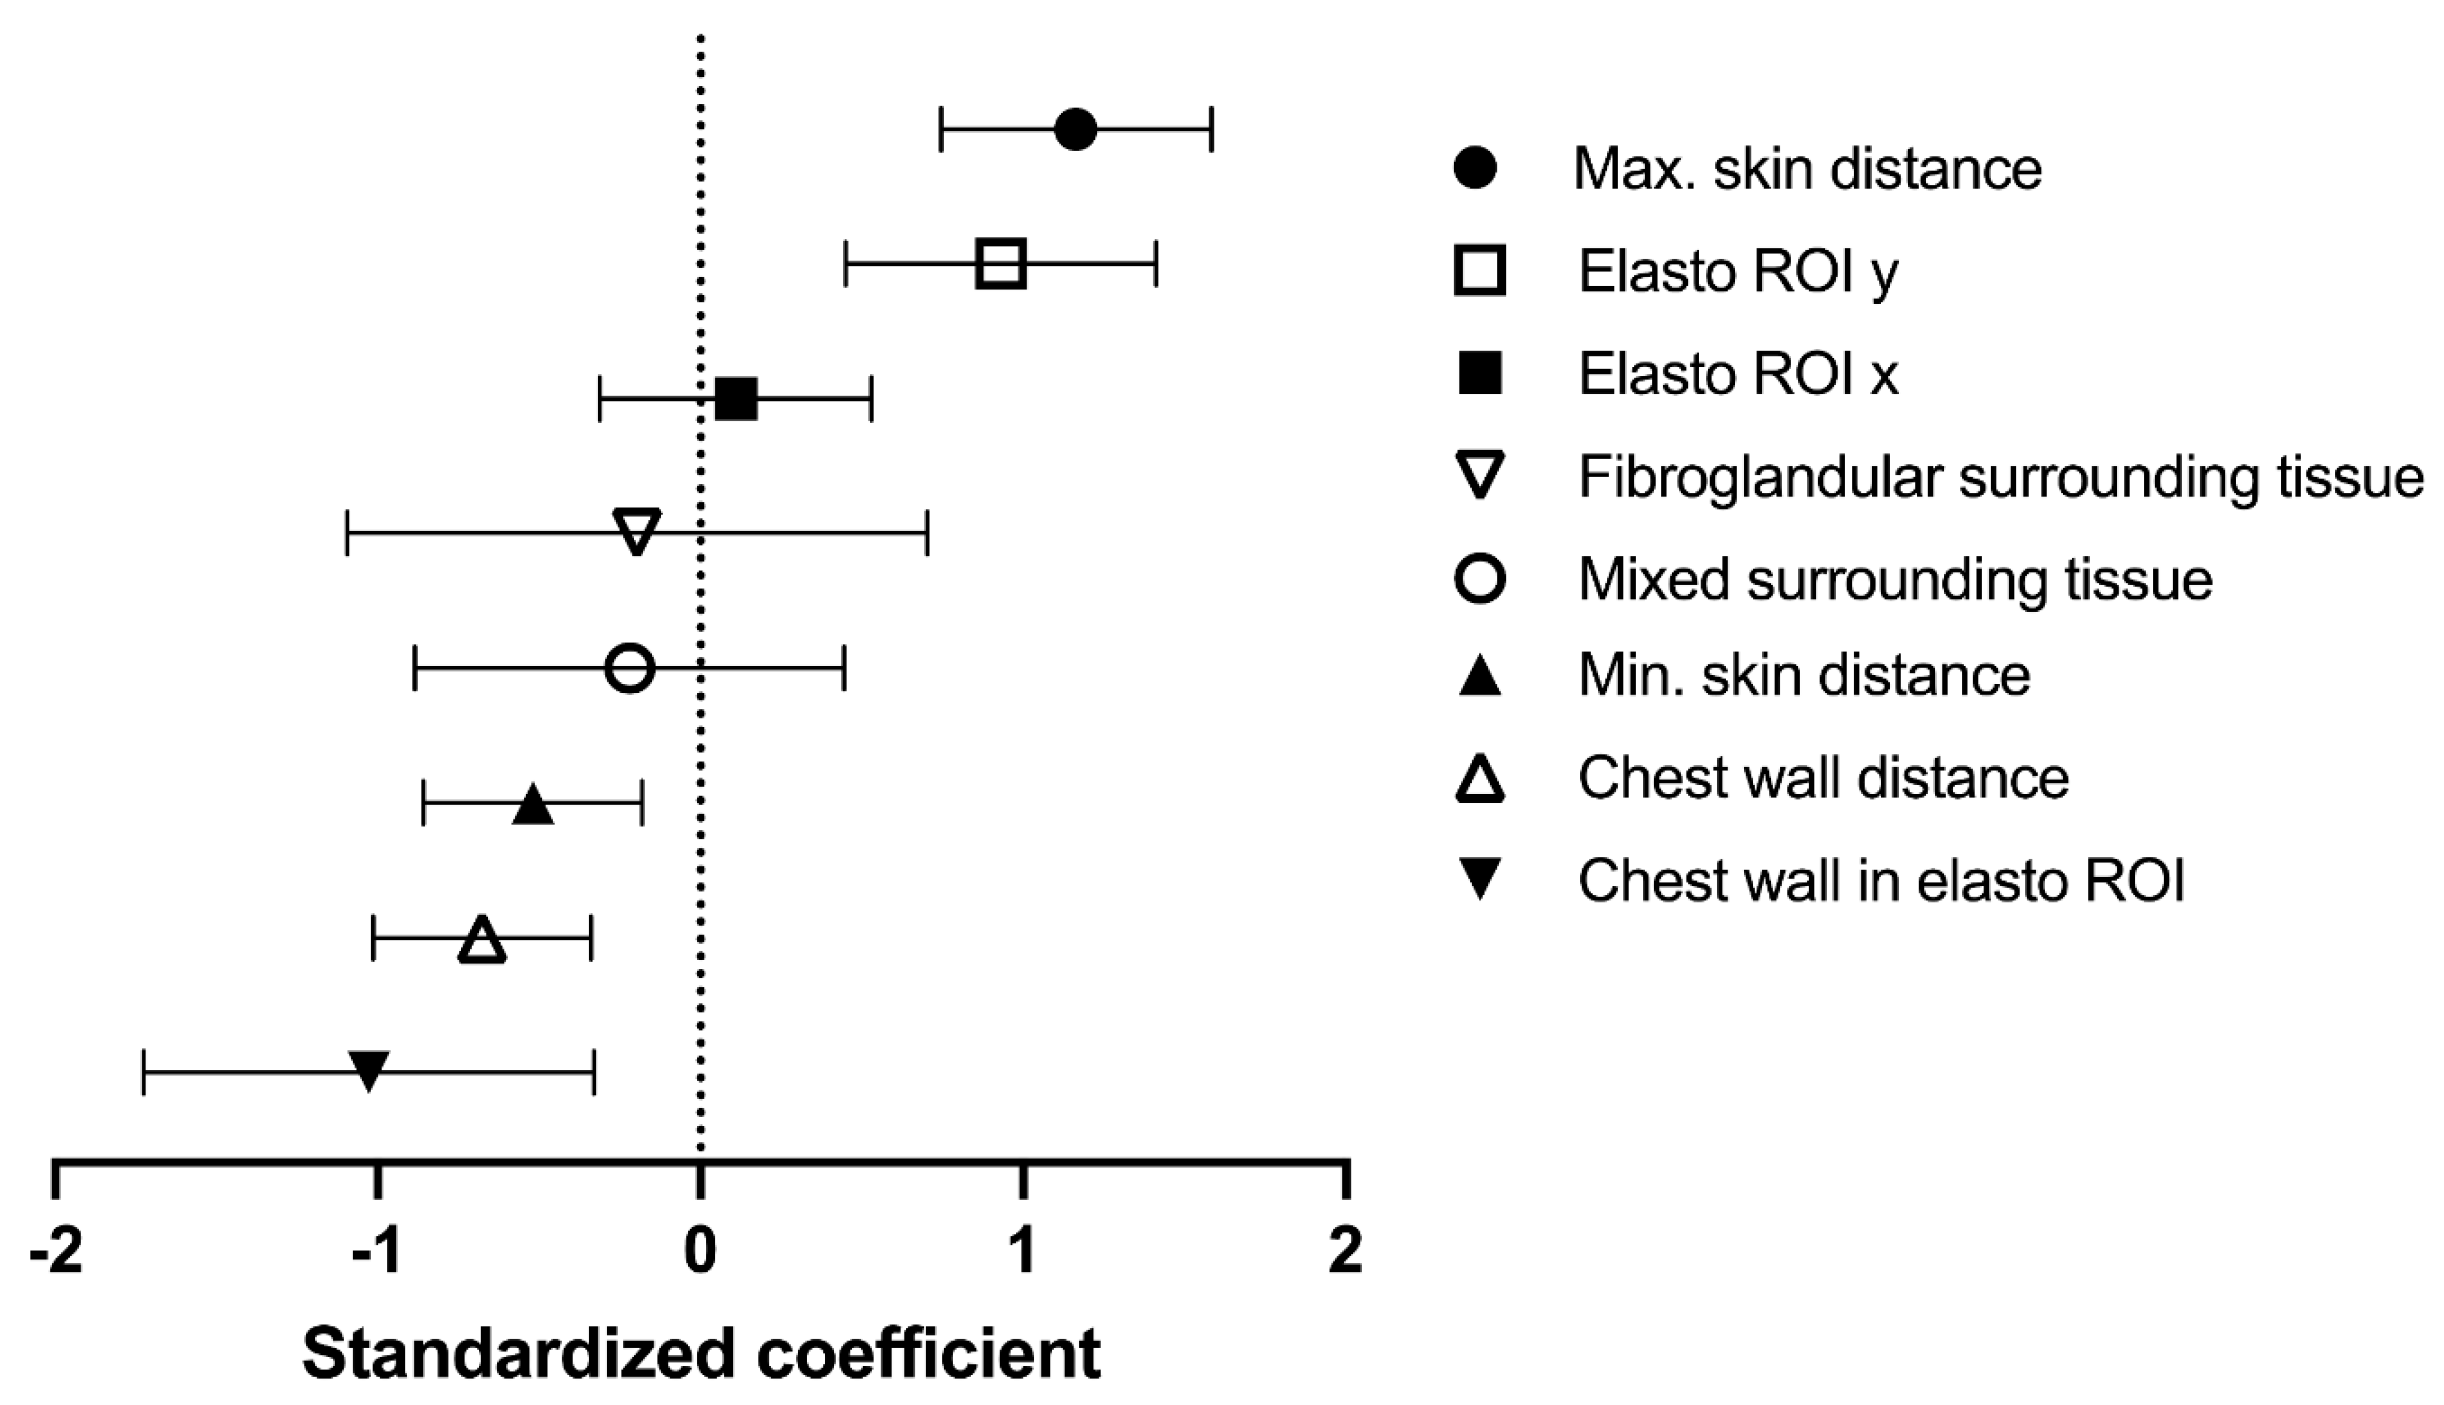

3.2. Covariates for Maximum Elastographic Peritumoural Halo Depth